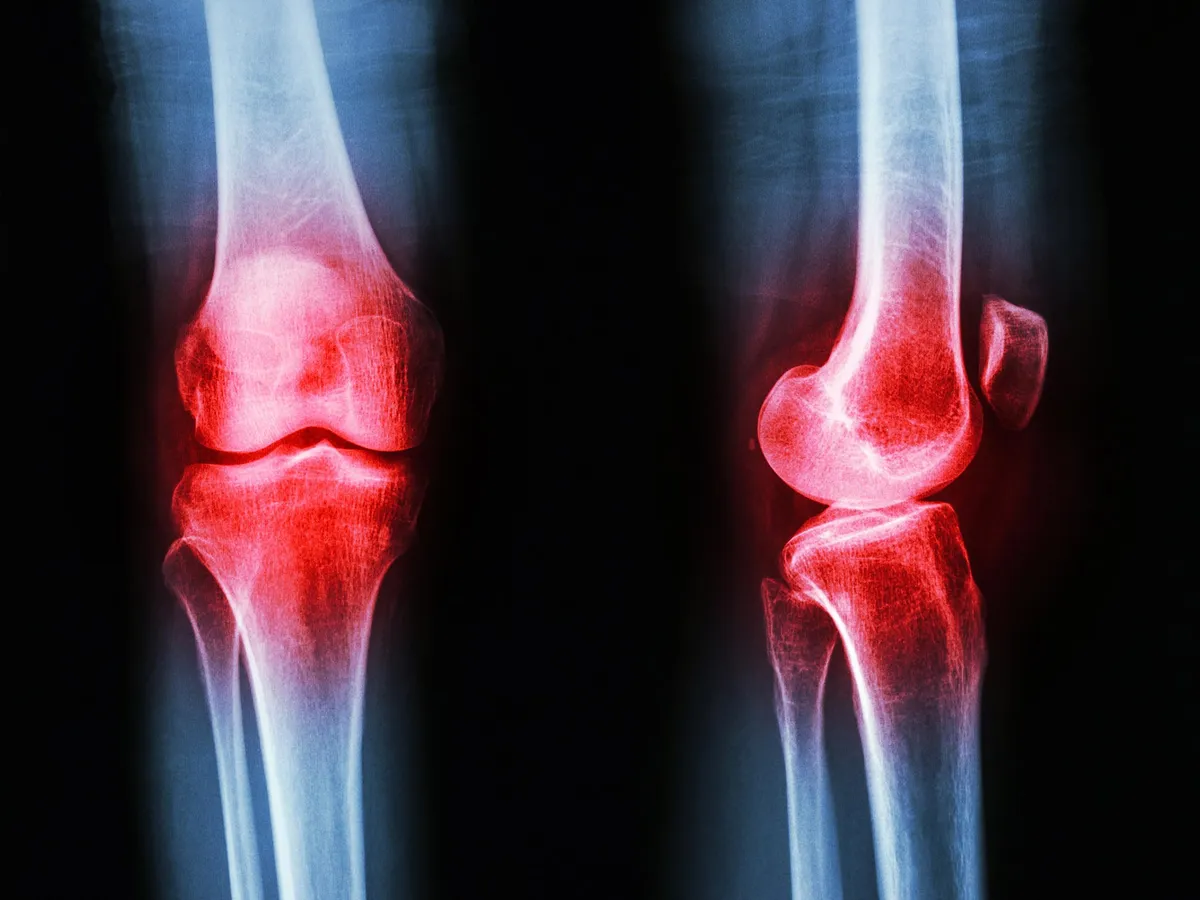

Rheumatoid arthritis is a brutal, chronic disease where your own immune system decides your joints are the enemy. The standard treatments often come with a laundry list of side effects, and sometimes, they just don't cut it. But what if the answer wasn't just about taming an overzealous immune system, but about rethinking how your body handles its fats?

When tested on rats with RA, the results were pretty compelling. Rats treated with OL showed significantly less joint swelling. Their cartilage and joint tissues, which usually take a beating, looked remarkably healthier. Even their thymus and spleen, crucial immune organs, showed signs of recovery. Because apparently that’s where we are now: making rats' spleens recover.